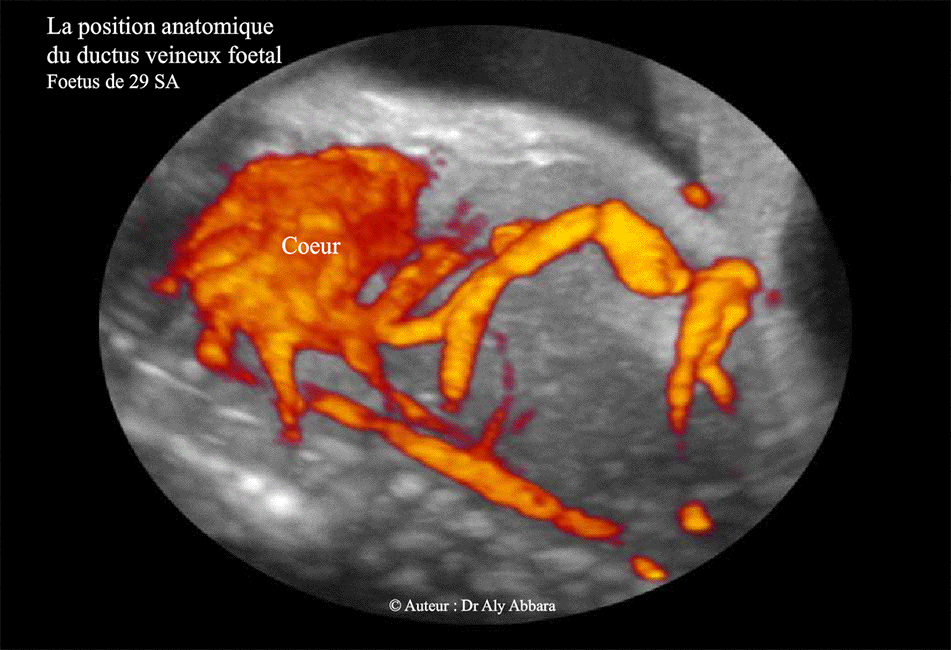

Ductus veineux et ses rapports anatomiques - 29 SA - Echographie

Images échographiques analysant la position anatomique du ductus veineux (canal veineux, branche de la veine ombilicale gauche) et son aspect anatomique durant la vie fœtale (29 SA dans le cas présent) :

Le canal veineux prend naissance de la veine ombilicale et après un trajet court se jette directement dans la partie terminale de la veine cave inférieure au niveau de terminaison des trois veines hépatiques ; ce site de jonction de la veine cave inférieure avec le ductus veineux et les veines hépatiques se trouve sous le diaphragme et à une distance très courte de l'oreillette droite (quelques centimètres chez l'adulte).

Le ductus veineux permet à une partie du sang oxygéné rapporter par la veine ombilicale de se jeter directement dans l'oreillette droite sans passer par le foie. Grâce au shunt droit-gauche, ce sang richement oxygéné, se dirige vers l'oreillette gauche à travers le foramen ovale pour ensuite être distribué à l'ensemble de l'organisme fœtal en utilisant le système circulatoire sanguin gauche (ventricule gauche > aorte > ...)